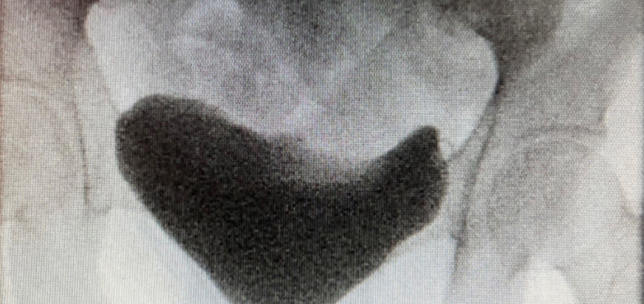

Paediatric Urology , Functional / Reconstructive Urology

Upper tract abnormalities

Functional / Reconstructive Urology

Functional and reconstructive urology